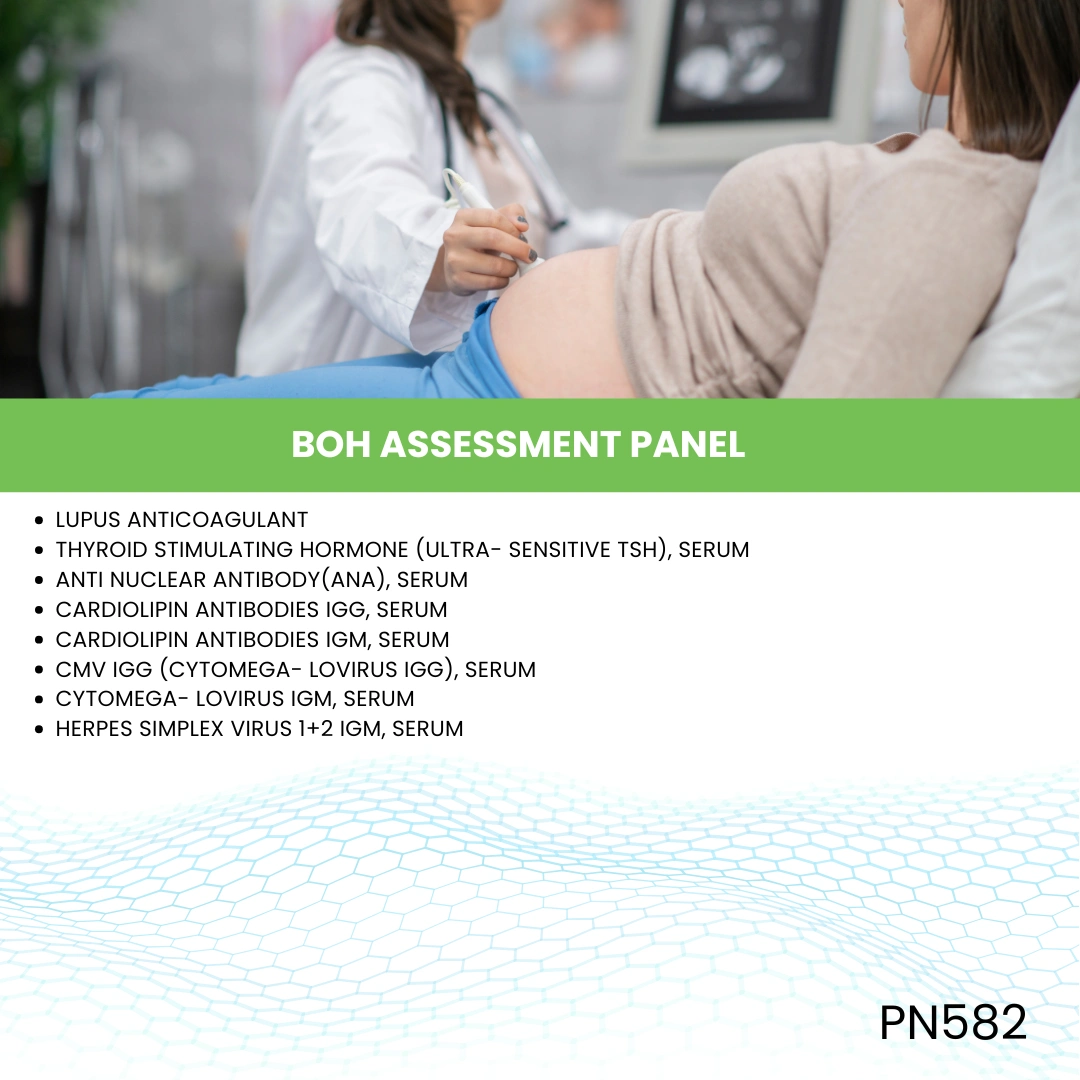

- Pregnancy Test

Popular Tests